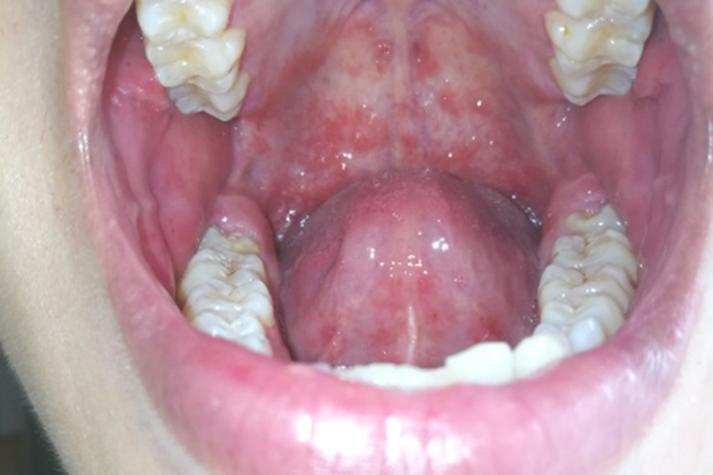

儿童口腔上颚红斑是何原因?

儿童口腔上颚(硬腭)出现红斑,可能由多种原因引起,从轻微的生理现象到需要治疗的感染都有可能,以下是几种最常见的情况,并附上文字描述和特征,帮助您进行初步判断。

- 外观: 口腔上颚、颊部、舌面等处出现乳白色、微凸起的斑片。

- 质感: 斑片看起来像牛奶凝块或豆腐渣,不容易被擦掉。

- 周围黏膜: 红斑(或白色斑片)周围的黏膜通常会有明显的发红、充血。

- 症状: 孩子可能会因为口腔疼痛而拒食、哭闹不安,有时伴有轻微发烧。

- 外观: 早期口腔上颚、舌头、颊黏膜、牙龈等处出现散在的、针尖大小的红色斑丘疹或水疱。

- 发展: 水疱很快会破溃,形成灰白色的小溃疡或糜烂面,周围有一圈红色的晕。

- 疼痛感: 溃疡会引起明显的疼痛,导致孩子流口水、拒食、哭闹。

- 伴随症状: 通常伴有发烧,手、脚、臀部或膝盖处出现典型的皮疹。